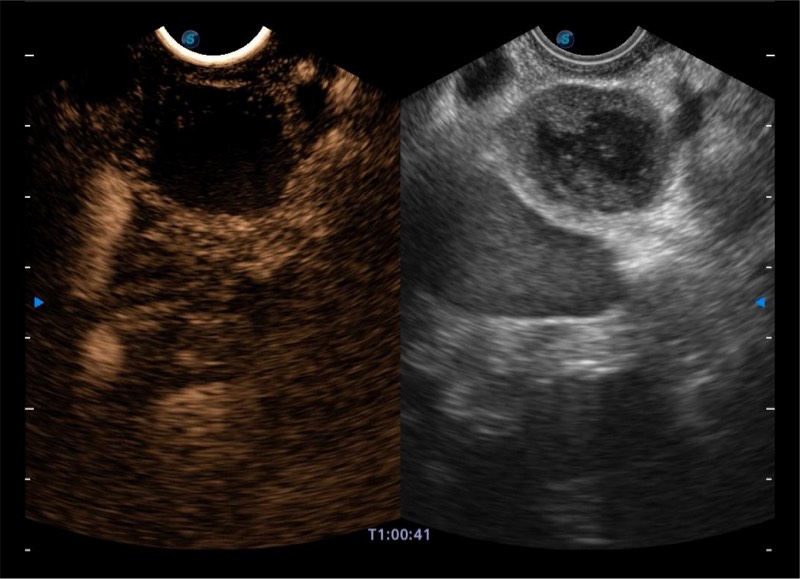

基于二十年的超声技术积累,银河集团官网提供了最新一代的独立超声主机,在提供高质量图像的同时满足多学科使用。具备常见多普勒技术并提供弹性成像、声学造影等高端影像技术。新一代传感器具有更强的抗干扰能力并减少图像伪影。

150°超声扫描角度

4-12MHZ宽频输出